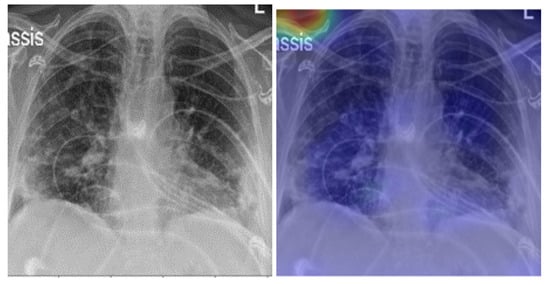

5. Model Explainability